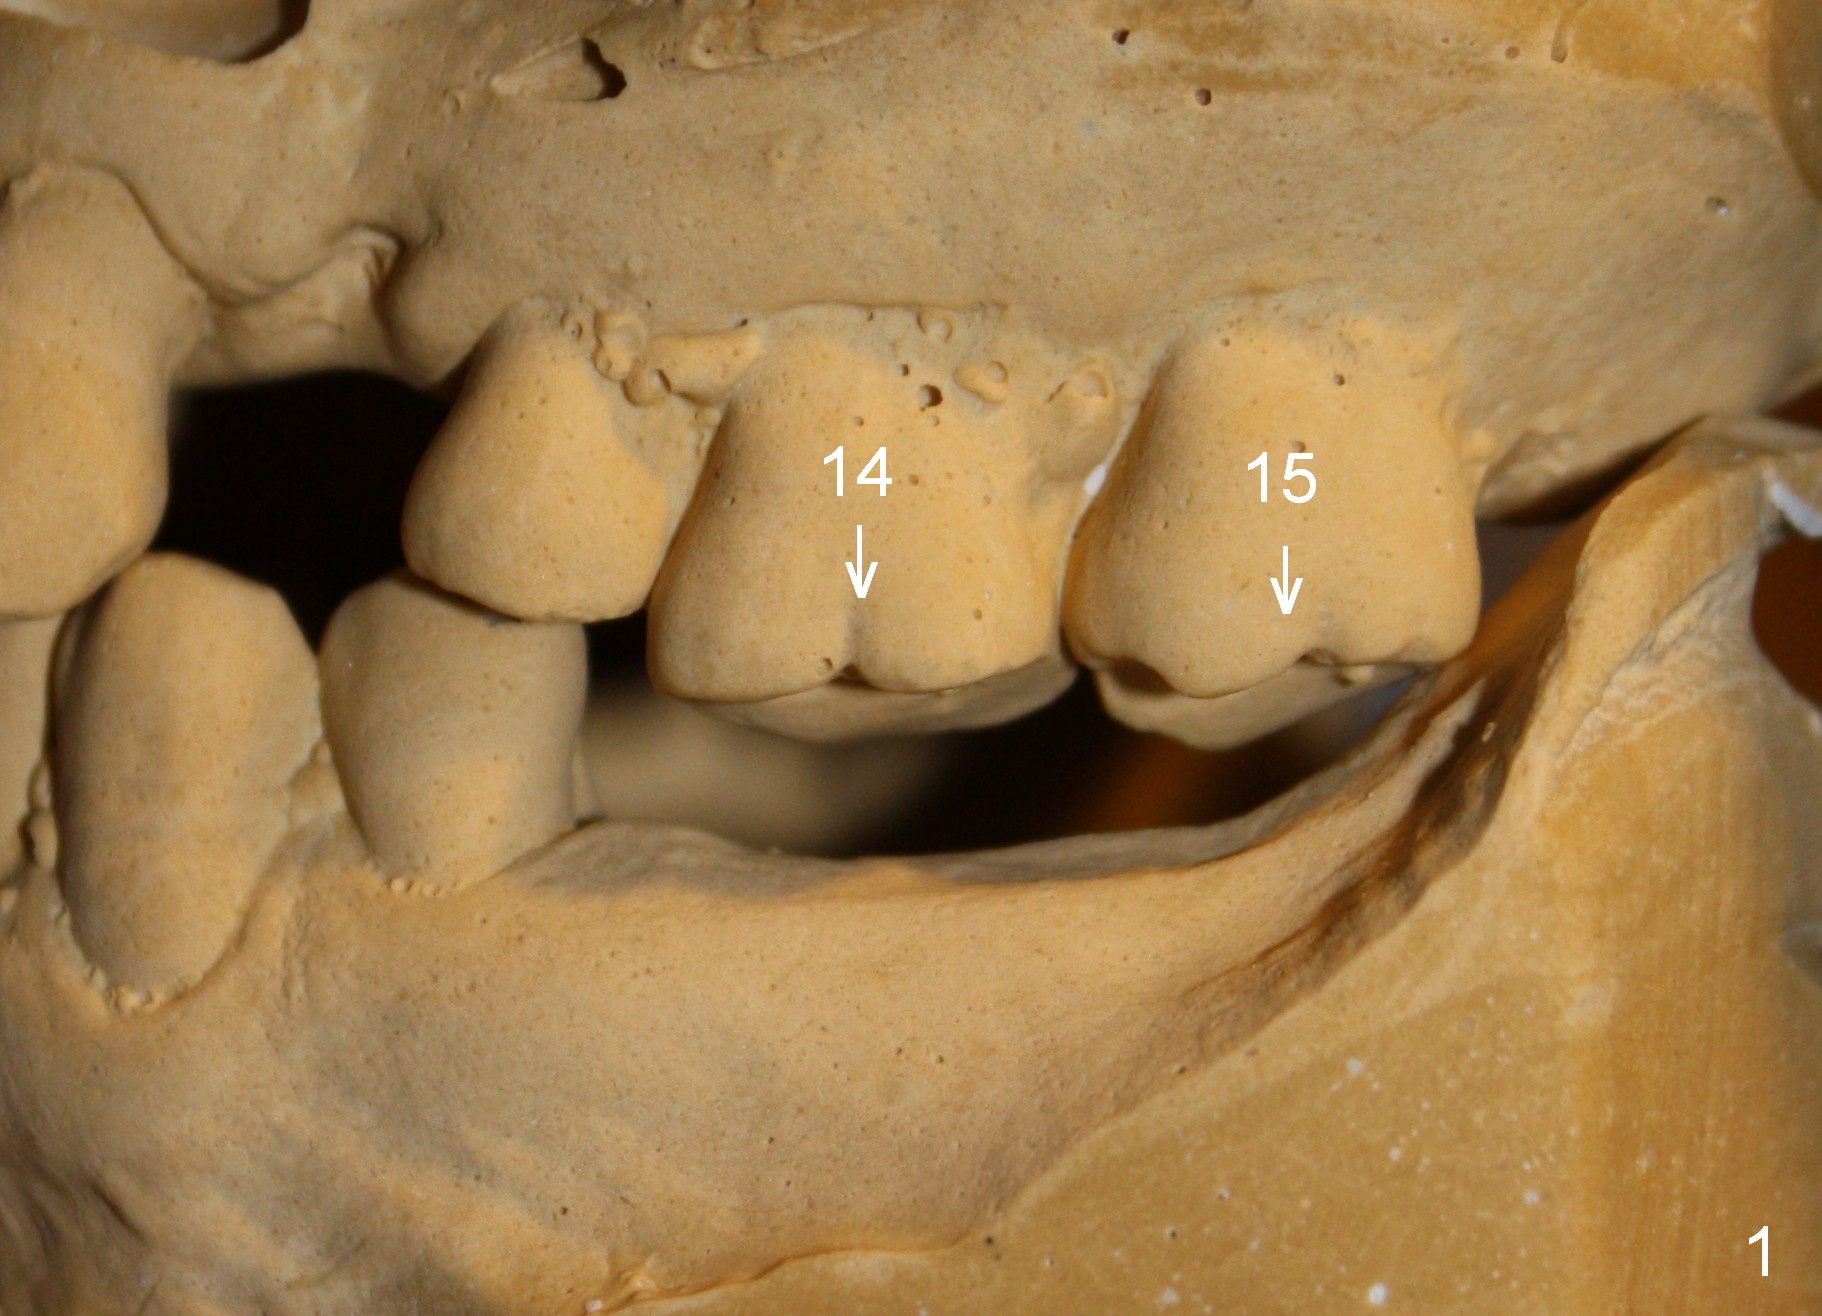

A 41-year-old man has chronic periodontits with bruxism. The teeth #14 and 15 are supraerupted (Fig.1 arrows) with furcal lesion (Fig.2 (CT) *). These 2 molars have guarded to poor prognosis. Due to insurance benefit limitation, we plan to save them temporarily with periodontal surgery so that bone loss would not get worse when the teeth are being intruded. After opposing implant placement (Fig.3), flaps are raised to remove calculus and granulation tissue (Fig.4, no bone graft). Twenty days later, three mini-implants are placed (Fig.5,6). The implant distopalatal to #15 is loose nearly 2 months postop (Fig.7 *) and retightened. The following month the same implant is placed higher for stability (Fig.8). The Intrusion takes <5.5 months (Fig.9,10).